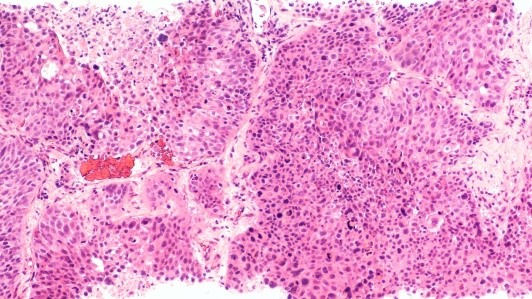

Для определения характера новообразования применяется биопсия. Исследуется биологический материал, полученный с соблюдением стерильности и минимальной травматизации.

Существуют разные виды биопсии. Тонкоигольная используется для цитологии. Толстоигольная позволяет получить больший объём материала. Инцизионная применяется для оценки структуры тканей.